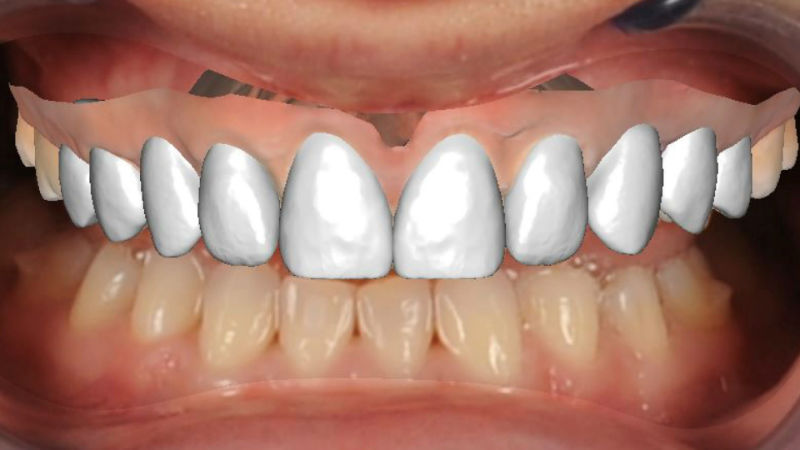

– Виртуално планирано ортодонтско лечение с алайнери – собствени зъби и зъби върху зъбни импланти